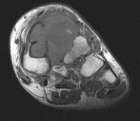

15 year old male with a left foot mass x >1yr.

It has recently grown in size and he has discomfort putting on hockey skates.